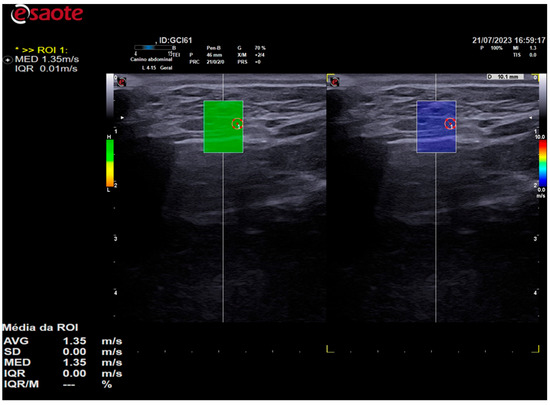

In all animals, shear-wave velocity measurements were only taken in high-quality regions, which were colored green. The color scale of the color elastogram ranged from blue (soft) to red (hard), passing through green and yellow (intermediate stiffness). To assess stiffness using shear-wave velocity, five samples of regions of interest (ROIs) were randomly selected, comprising different portions of the thyroid. These samples were selected using 0.2 cm diameter circles, as shown in Figure 5. The shear-wave velocity values of the analyzed portions were evaluated by the equipment’s software and expressed in m/s.

Figure 5. A 2D shear-wave elastography image of the right thyroid lobe of a 10-year-old dog is presented. The elastographic image on the left shows the quality map of the QelaXtoTM 2D software, which is colored in green and indicates high quality for measuring shear-wave velocity. Four ROIs were selected to measure shear-wave velocity, as indicated by the circles on the elastographic image. The right side of the elastographic image displays a color elastogram (qualitative) from the QelaXtoTM 2D software, colored in blue, indicating that the thyroid parenchyma had low stiffness (soft).